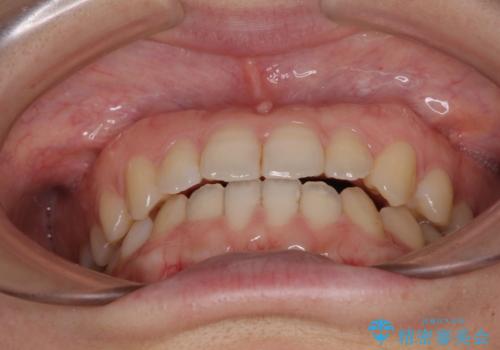

前歯のクロスバイト インビザラインによる矯正治療

- 前歯のクロスバイトとデコボコを気にして来院された患者様です。

骨格的に下顎前突傾向であるため、自己管理が煩わしくないようであれば、インビザラインによる矯正治療がお勧めとなります。

インビザラインを用い、下顎歯列を後方に移動させながら全市の被蓋を改善し、歯並びを整えていくこととしました。

途中マウスピースが使用できず、来院されない期間があり、治療期間は長くかかりましたが、無事に治療を終えることができました。